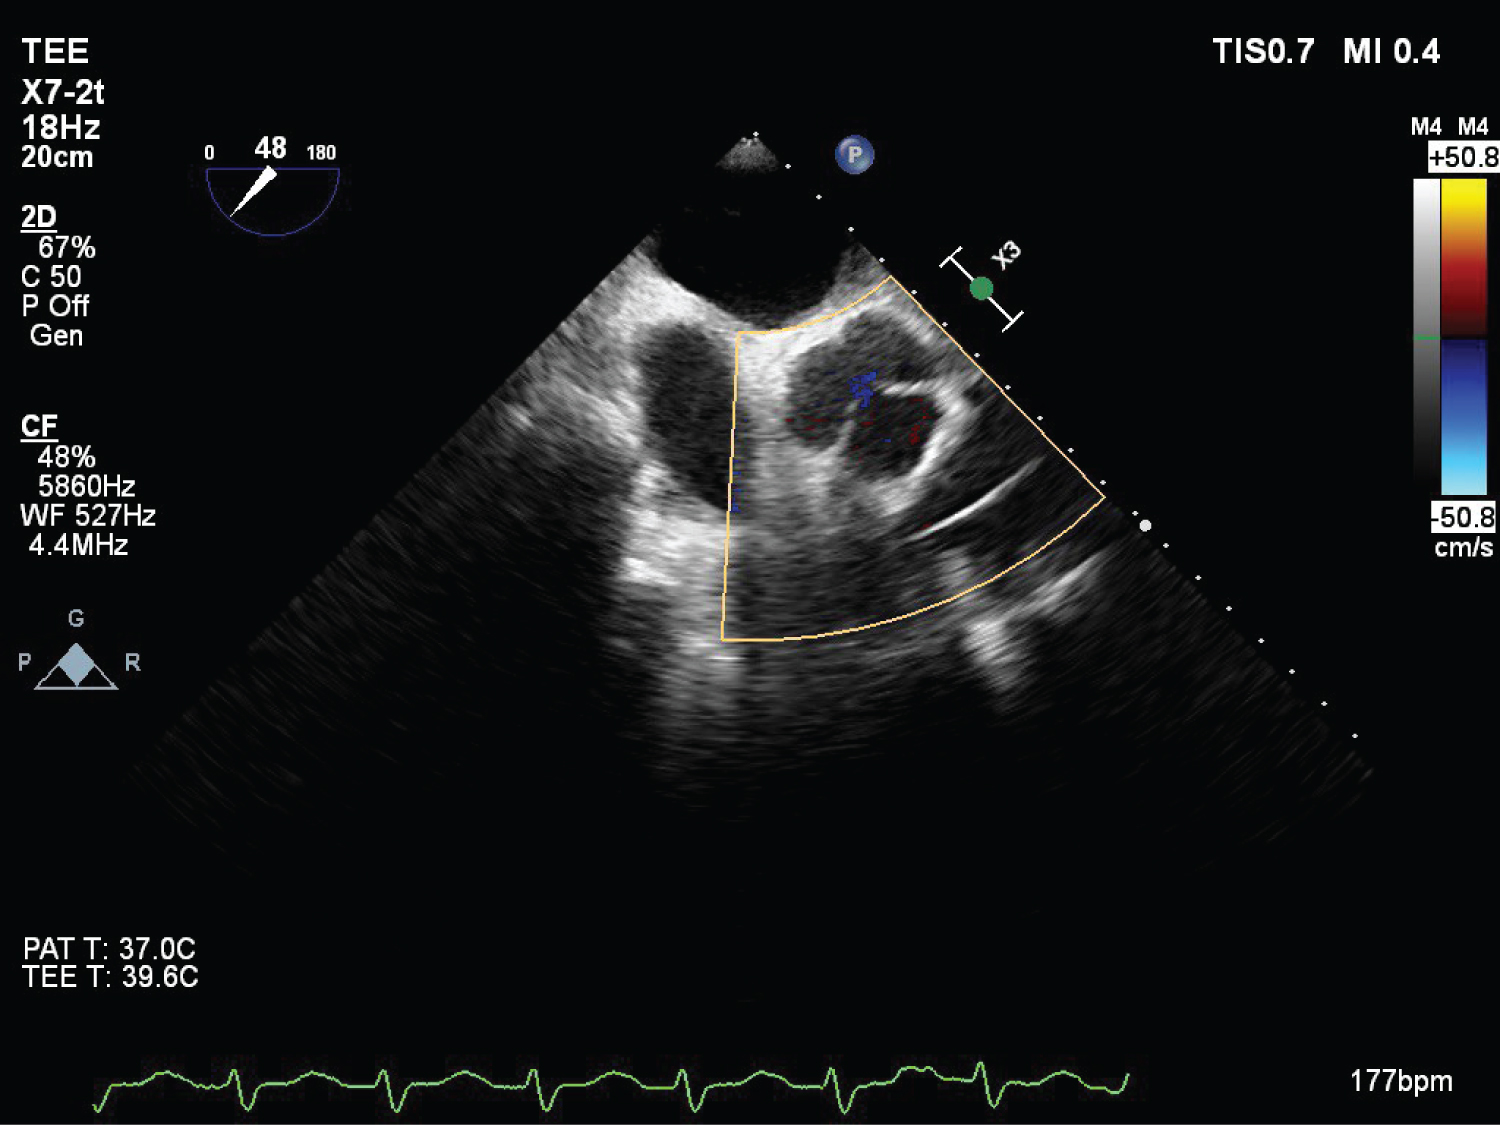

On echocardiography, aneurysmal appearance of the involved sinus and the presence of a “windsock,” protruding into the receiving chamber are characteristic of RSOV [7] (Figure 1, Figure 2, Figure 3, Figure 4 and Figure 5) ( Video 1 and Video 2 ).

Figure 4: (TEE) Mid esophageal RV inflow outflow view post surgical correction of RSOV and VSD repair with RV ridge resection. View Figure 4

On TEE evaluation adequate RSOV repair and no residual VSD shunt was confirmed. Patient came off cardiopulmonary bypass uneventfully. Patient’s self-heart rhythm was restored, hence pacing was switched off.